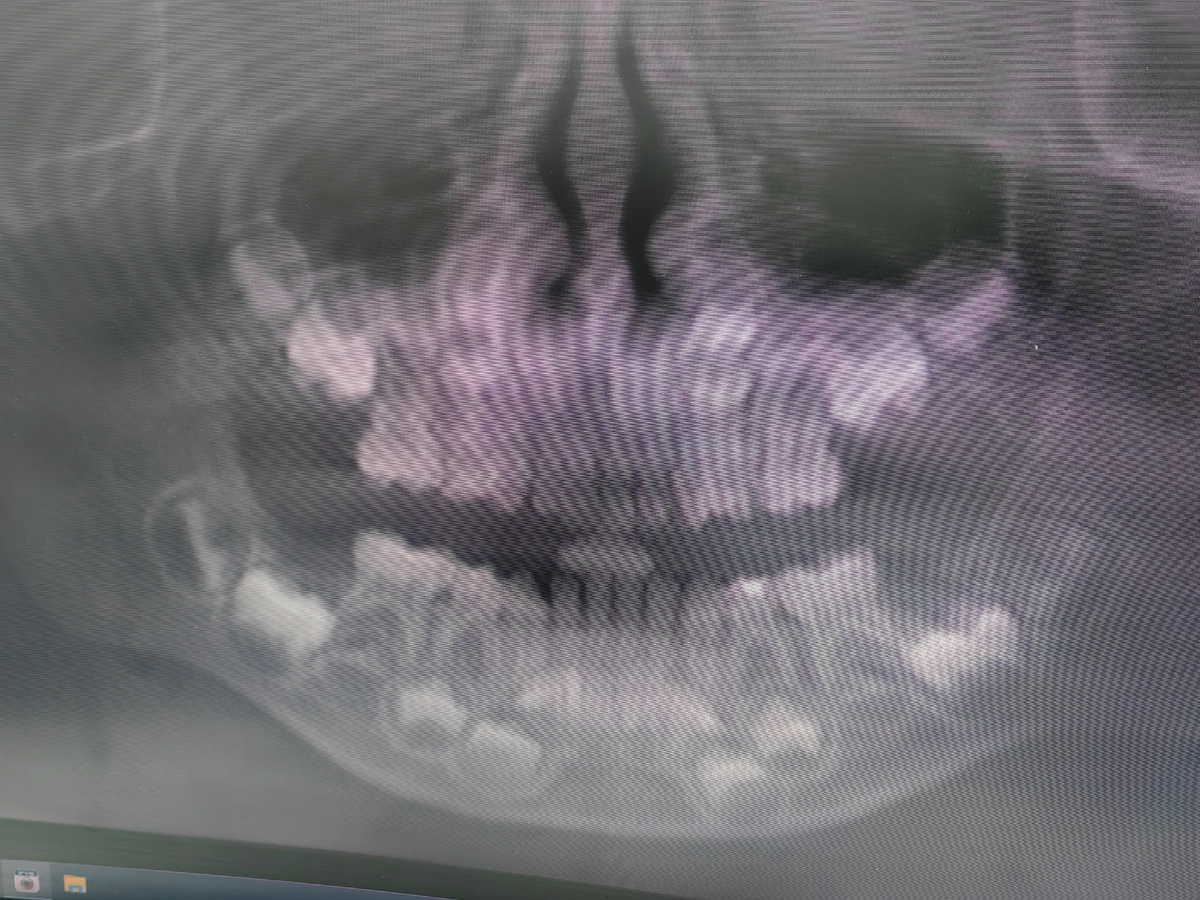

Так выглядит панорамный снимок челюсти Маргариты.

При просмотре снимка компьютерной томографии пятёрки всё-таки были найдены, они прятались за клыком и шестёркой с другой стороны, но это никак не отменяло моего ужаса, что переднего зуба у Маргариты нет и не будет в перспективе!